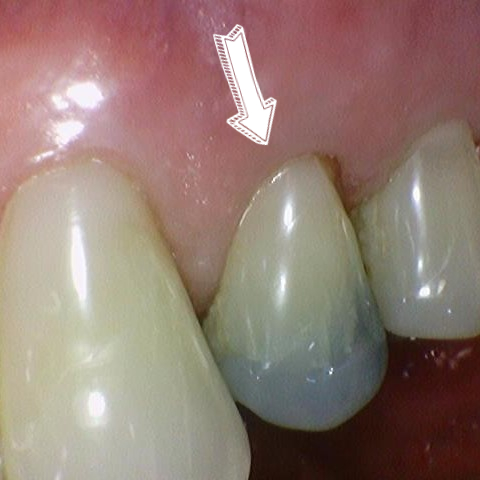

신경치료 후 크라운을 하지 않아 치아가 반으로 쪼개지고 염증까지 생긴 상태